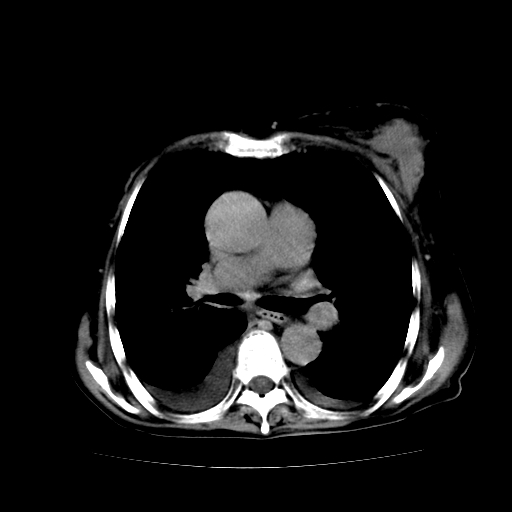

女70y乳腺ca(针吸活检)

多部位转移瘤的诊断可以肯定,我的疑问是:双肺对称高密度影及胸水是否为心衰肺水肿,病人体虚弱,不好意思图象传的乱![em9]

肺部病变为淋巴转移,肝脏转移,及局部淋巴转移。胸水可能为淋巴回流受阻(血性的考虑胸膜转移)

癌性淋巴管炎,肝脏转移,瓷胆囊

1)左侧乳腺癌并左侧腋窝及纵隔淋巴结转移,两肺淋巴道转移(癌性淋巴管炎),肝脏多发性转移。2)双侧胸腔积液。3)慢性胆囊炎。

癌性淋巴管炎,胸膜转移.肝内转移,纵隔及腋窝淋巴结转移

1、左侧乳腺癌;

2、左腋窝、纵隔淋巴结肿大(转移性);

3、双肺癌性淋巴管炎;

4、双侧胸腔积液(考虑淋巴回流障碍所致);

5、肝转移瘤;

6、瓷胆囊。

1)左侧乳腺癌并左侧腋窝及纵隔淋巴结转移,肝脏多发性转移。2)双侧胸腔积液伴双肺蝶翼样磨玻璃高密度影,双侧肺门血管影增粗(图像不全,肺门层面没纵隔窗),考虑心功能不全所致。3)慢性胆囊炎伴壁钙化。